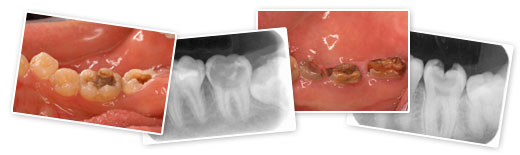

残念ながら、自覚症状(冷たいものがしみる、噛むと痛い、穴が開いたなど)が出たときには、かなり進行しているのが実情ですので、早期発見・早期治療が重要になります。

大きな虫歯になる前にできるだけ早く歯科医院へ向かいましょう!